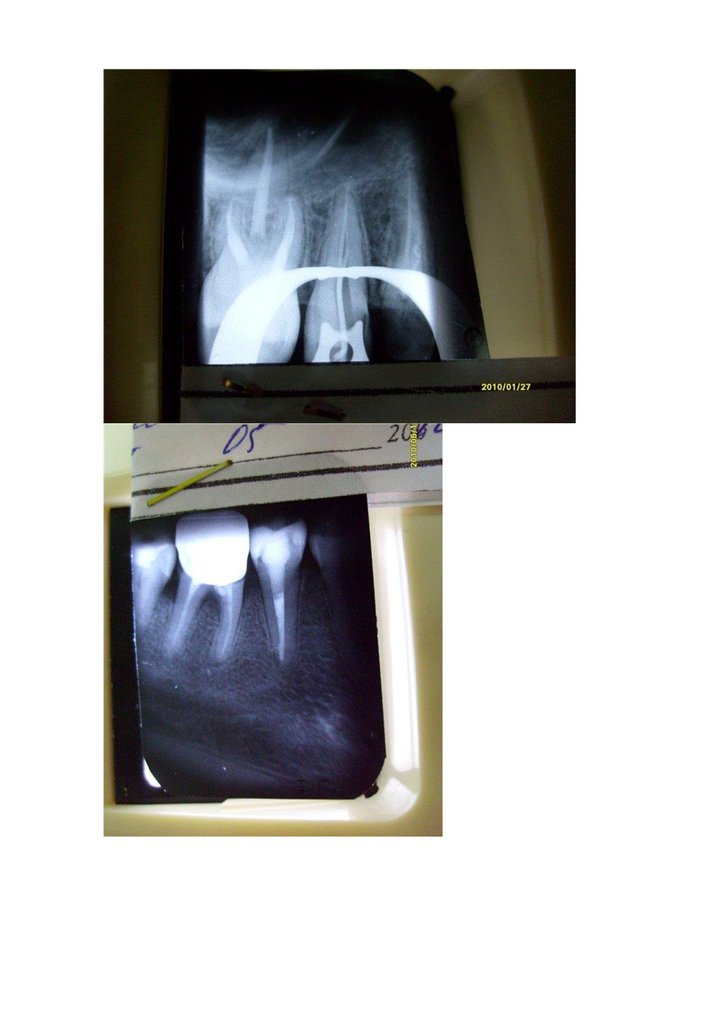

Тут видно как в медиальном корне 36з заполнилось поднутрение

Здесь просто каналы.